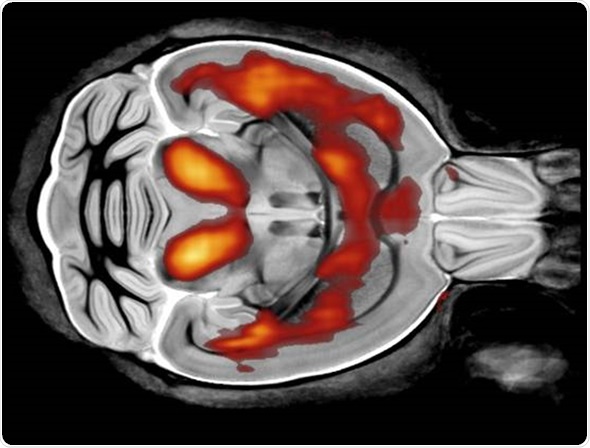

In terms of research projects, what I'm really interested in is a technique called diffusion MRI. The beauty of using this technique is that it can give you information about the microstructure of tissue.

On a clinical scanner, the MRI voxel is probably about a millimeter in length, whereas the kind of spatial information that we want is a thousand times smaller than that, it’s about a micron in size.

So, how do we get spatial information on the scale of microns when the actual voxel is about a millimeter long? We use diffusion MRI, because we can look at the way water diffuses within the cell.

If you have an axon for example, which is a long, thin tube, water is relatively free to diffuse along it, but it is restricted when it comes to going across the axon.

By looking at different diffusion times, we can infer the size of the axon. In particular, axon diameter estimates are important in the diagnosis of many neurodegenerative diseases.

Another new area I’m looking at that is associated with microstructure is cell permeability, which is abnormal in many neurodegenerative diseases such as multiple sclerosis.

We hope to be able to use these sequences in many neurodegenerative diseases, as well as things like stroke and heart disease. It is going to be a useful tool that utilizes very interesting physics, and that's what I'm really interested in - using clever physics and MRI.